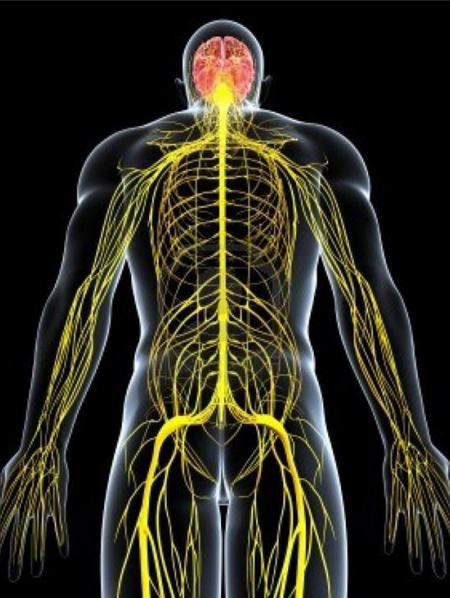

Evaluación y tratamiento especializados para toda la gama de problemas en el cerebro, columna vertebral y nervios periféricos....

Neurocirugía y sistema nervioso

El reconocimiento de la neurocirugía como especialidad, se debe a los logros de Harvey Cushing, quien el 18 de noviembre de 1904 presentó su experiencia ante la Academia de Medicina de Cleveland, en un trabajo que llamó « The Special Field of Neurosurgery ». Más